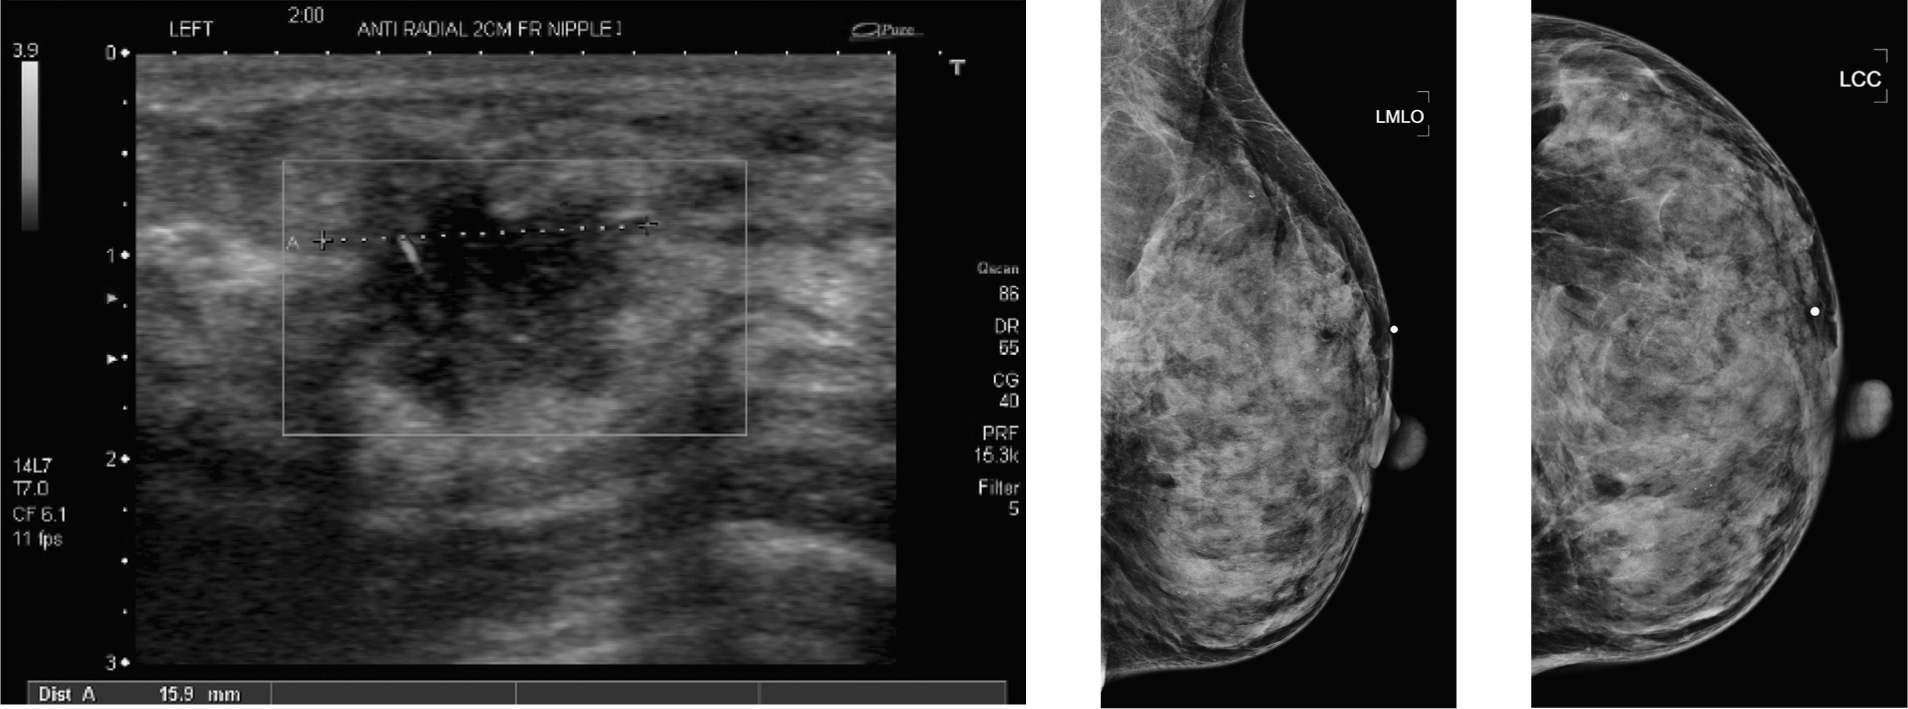

From radiologykey.com

Difficult Cases Radiology Key Painful Lump Breast Postpartum Pitties, a rare side effect of breastfeeding that results in armpits swollen with breast milk. Most breast lumps turn out to be nothing serious, but about 20% of lumps are malignant (cancerous). You may also be able to feel a hard or thick lump in your breast — that’s likely the clogged milk duct that caused the mastitis. Mastitis, which. Painful Lump Breast Postpartum.